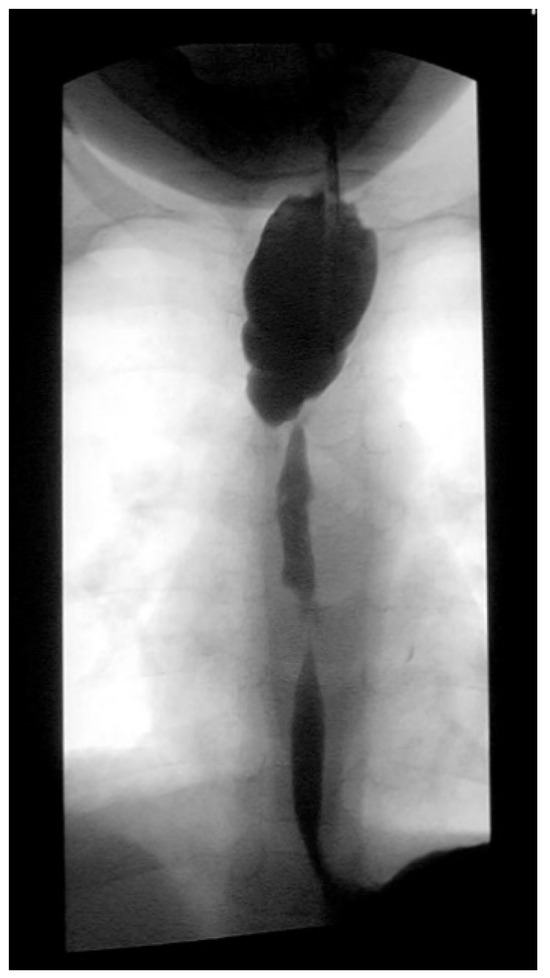

Three weeks before surgery, the children were transferred from Africa to Switzerland for the evaluation of their nutrition status, as they eventually needed to be fed carefully and progressively. A thoracic X-ray and an esophagogram are performed (Figure 2). Intubation allowed an endoscopic evaluation of the grade of esophageal and pharyngeal stenosis and mobility of the vocal cords (Figure 3). This evaluation was done with our ear nose and throat (ENT) colleagues, and eventual tracheotomy was discussed for very high stenosis of the larynx without residual damage to the esophagus.

Figure 2. Preoperative esophagogram.